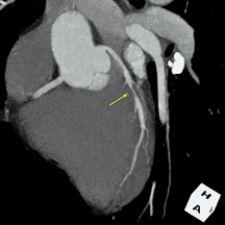

3-D volume rendering showing mid left anterior descending artery (LAD) stenosis, created using TeraRecon software.

In the past, cardiac imaging necessitated specialized equipment such as electron-beam CT. Advances in multidetector CT [MDCT] have now allowed for acquisition of motion-free sub-millimeter resolution images of the heart with ECG gating in one breath-hold. ECG gating also allows for cine imaging, assessing ventricular contractile function by reconstruction of images at different cardiac phases. The isotropic voxel nature of MDCT allows for ease of 3-D multiplanar reconstructions (MPR) and volume rendering techniques (VRT), increasing the diagnostic confidence. Due to high resolution and short acquisition time, ECG-gated MDCT holds a distinct advantage over cardiac MRI in morphological coronary imaging.

In patients less than 50 years old, a small but significant number have significant angiographic coronary artery disease (CAD), but do not have coronary calcification on CT. Even in older patients with unknown CAD, up to 10 percent may have noncalcified plaques. It is therefore advisable that contrast should be used to evaluate significant stenoses caused by soft plaques, especially in younger patients, if there is no contraindication.

MDCT has several limitations in evaluating CAD. The dose for 64-slice cardiac CT is unfortunately [high], even with pulse modulation. The presence of arrhythmia also will markedly decrease the quality of ECG gating and the corresponding quality of images. A high heart rate above 70 will also decrease the diagnostic quality of the study. Other limitations include contrast adverse reactions and exacerbation of renal insufficiency. Extensive coronary calcification can also cause blooming artifacts, preventing adequate evaluation for significant stenosis. The moderate positive predictive value — 75 percent — limits utility of MDCT for assessing significant obstruction of native coronary arteries in high-risk patients.